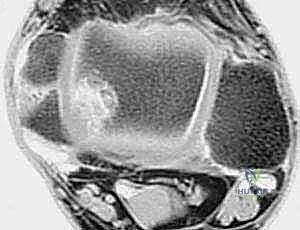

* التصوير بالرنين المغناطيسي (MRI): هو المعيار الذهبي. يوضح بدقة متناهية حالة الأربطة (تمزق جزئي، تمزق كلي، أو تندب)، ويساعد في الكشف عن أي إصابات مصاحبة مثل تمزق الأوتار الشظوية أو إصابات الغضروف المفصلي (Osteochondral Lesions).